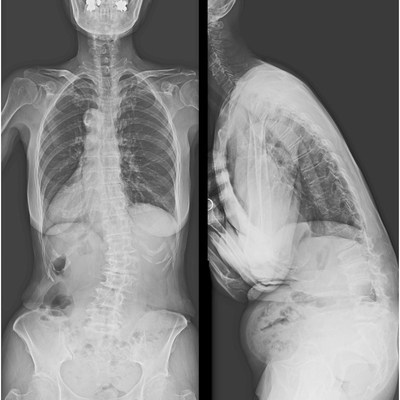

Click on an image below to view more info.